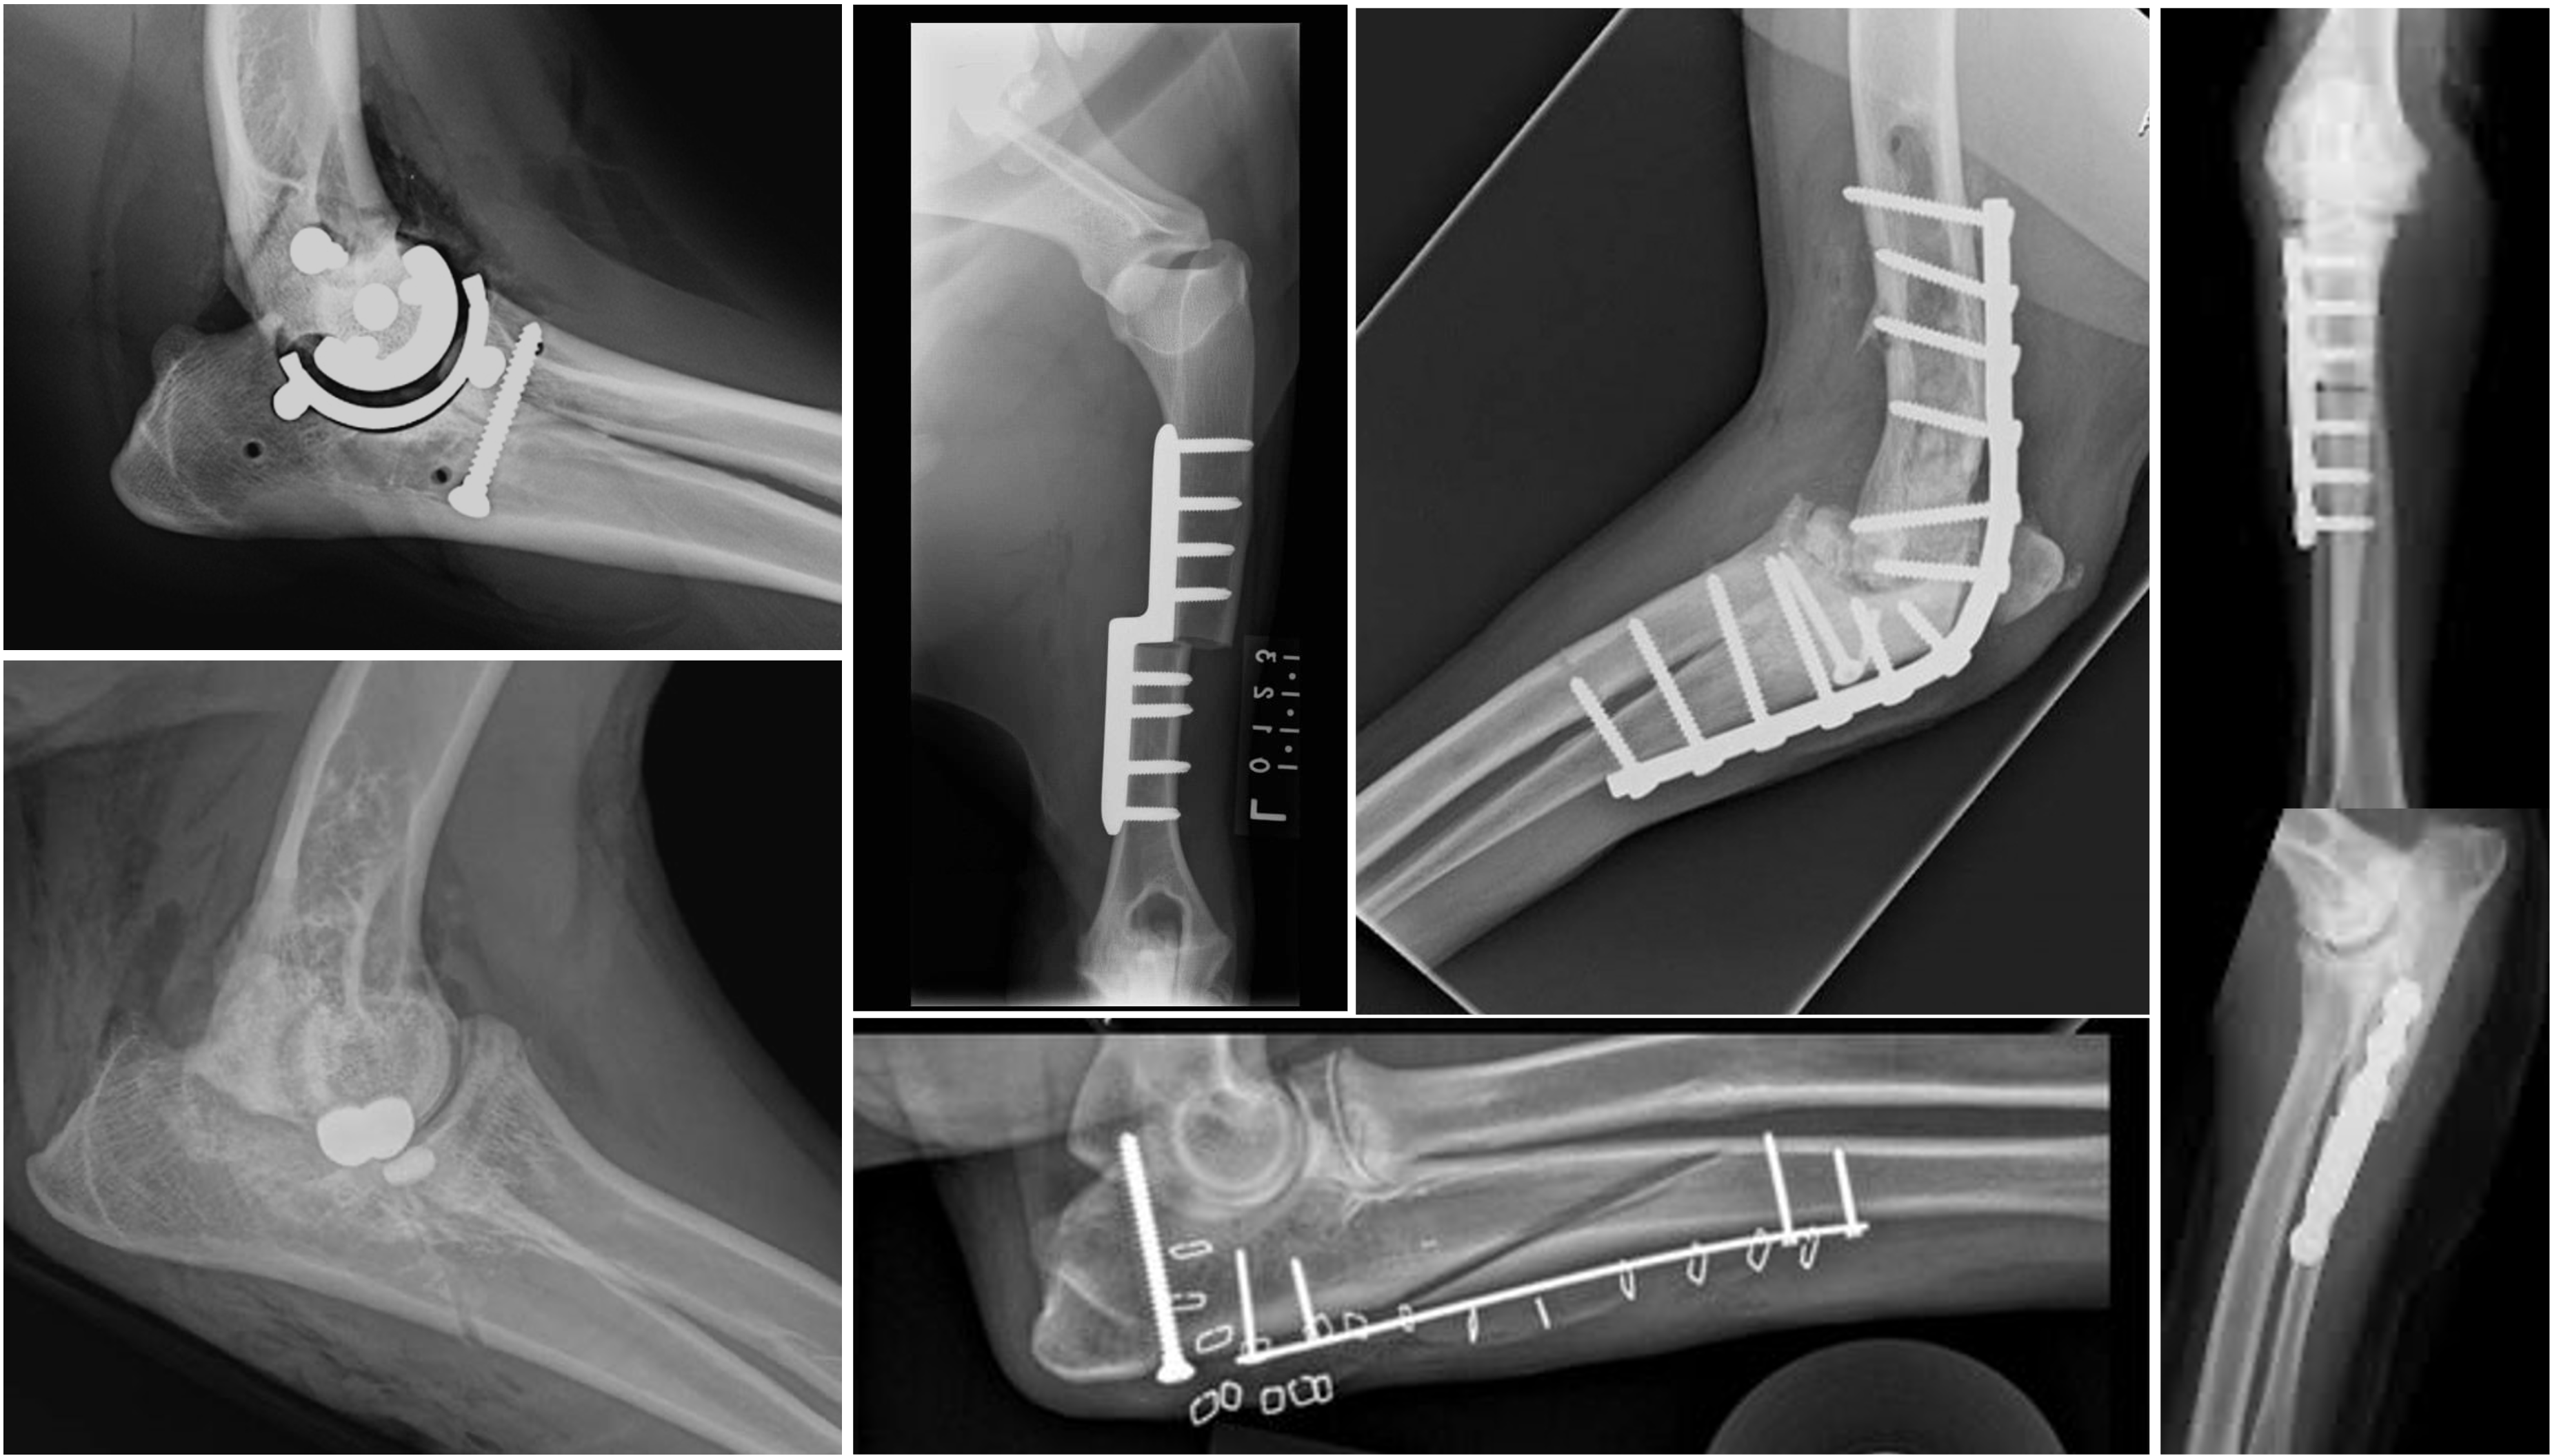

The reviewed procedures included axis-shifting osteotomies (e.g., proximal abducting ulnar osteotomy [PAUL] and sliding humeral osteotomy [SHO]), partial resurfacing (canine unicompartimental elbow [CUE]), salvage options (total elbow arthroplasty [TEA] and arthrodesis), and ulnar osteotomy. Here's a breakdown based on the evidence:

• Canine Unicompartimental Elbow (CUE): Three studies (one prospective with 103 cases, one retrospective with 48, and one case series). Success rates ranged from 91%–98%, primarily via subjective assessments like the Liverpool Osteoarthritis in Dogs (LOAD) questionnaire and physical exams. NNH was 7.6, indicating relatively high harm risk (i.e. one in every 7-8 procedures resulted in a major complication). This procedure resurfaced the medial compartment, showing the strongest evidence overall.

• Sliding Humeral Osteotomy (SHO): Five studies (one small prospective with long-term PVF data on seven cases, plus larger retrospectives). Success varied from 43%–82%, with lameness scores as the main metric. NNH was 9.5.

• Proximal Abducting Ulnar Osteotomy (PAUL): Two studies (both prospective). Outcomes included owner satisfaction and Canine Brief Pain Inventory (CBPI) scores, with high success (76%–98%) but limited case numbers.

• Total Elbow Arthroplasty (TEA): Two studies (one prospective, one retrospective). Assessed via multifactorial scores and surgeon evaluations; success was high but evidence weak due to small samples.

• Arthrodesis: Two retrospective studies. Measured by owner satisfaction and lameness improvement (e.g., LOAD); viable for salvage but with higher complication risks.

• Ulnar Osteotomy: One prospective study using lameness scores; limited data.